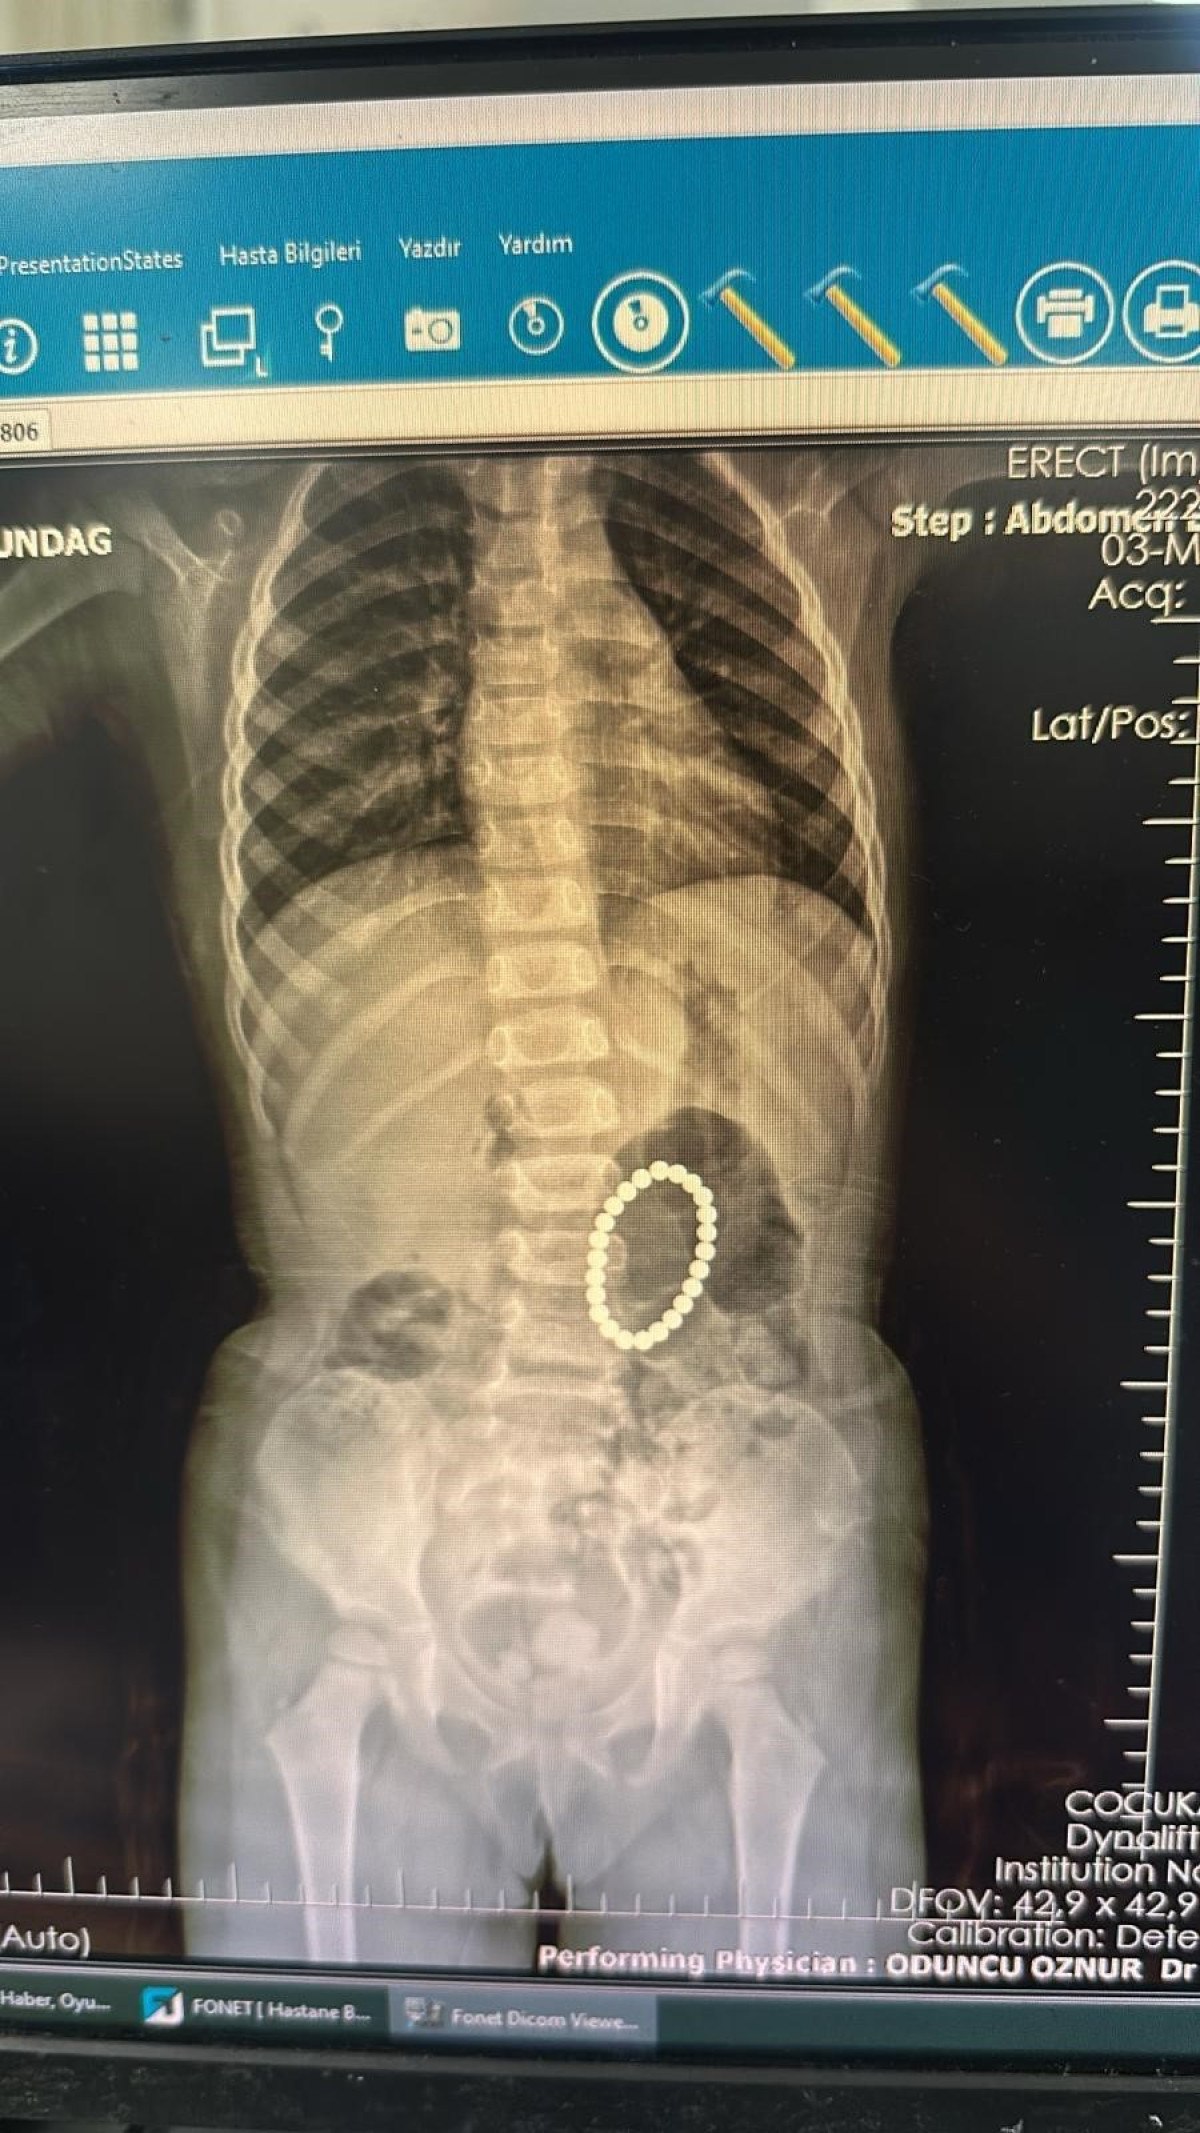

MİDESİNDEN 24 TANE MIKNATIS ÇIKTI

Yapılan endoskopide küçük kızın bağırsaklarında ve midesinde bileklik şeklinde yabancı cisimlerin olduğu belirlendi.

Ameliyata alınan Rumeysa Altundağ’ın bağırsakları ve midesinden 24 adet renkli oyuncak mıknatıs çıkartıldı.

Mıknatısların bağırsaklarda kısmen delinmelere neden olduğunu belirten Dr. Özkaya, “Hastamız 4 yaşında kız hasta. Yoğun karın ağrısı nedeniyle Şırnak’ta devlet hastanemize başvurmuş, yapılan tetkiklerinde yabancı cisim yuttuğu tespit edilmiş.

Bunun üzerine endoskopi yapılmak üzere hastanemize Gastroentoloji bölümüne sevk edildi. Endoskopi sırasında tespit edilen yabancı cisimlerin renkli mıknatıslar olduğu, yarısının da midede gözükmediği görüldü. Hastamız 24 tane renkli küçük mıknatıs yutmuştu.

Endoskopi işleminden sonra hastamıza operasyon planladık. Yaptığımız ameliyatta da farklı zamanda yutulan mıknatısların yarısının midede yarısının bağırsaklarda olduğu ve bunların birbirine yapışarak bağırsak kısımlarında delinmelere neden olduğu görüldü.